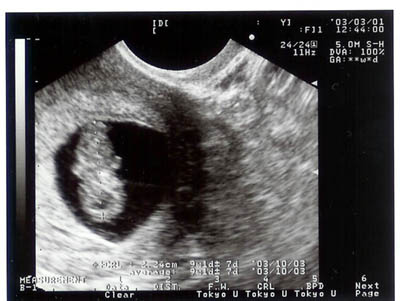

平成15年3月1日(土) 9週目

手足が動いていたって。

順調に育ってるって。

だいぶ大きくなった。手足が動いているのがわかるって。 |